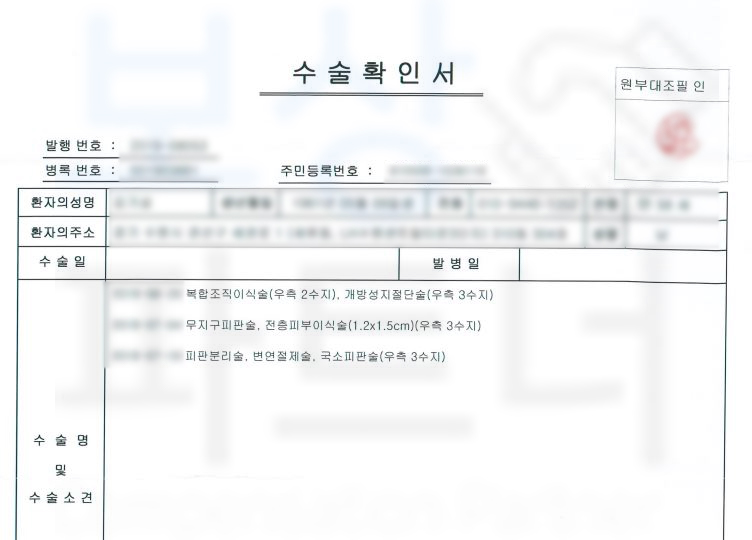

보상파트너에 연락주신 김@@님은 2수지 3수지 원위지골 골절 S62641 S682 진단받아 수술을 받게 되었습니다.

손가락에 철심 즉 핀고정은 안한신 상황이었습니다. 보상파트너는 먼저 김@@님의 보험증권을 받아 분석해드렸습니다.

해당사건은 굳이 장해진다서 발급 없이 영상CD와 함께 손해사정서 및 증빙자료를 송부하였습니다.